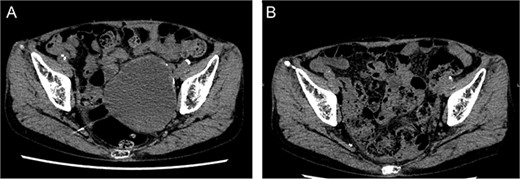

She underwent surgery under general anesthesia. A midline abdominal incision and an intraperitoneal approach were employed. The retroperitoneal space was accessed from the lateral side of the sigmoid colon to reach the CIA. The aneurysm was incised midway. The hematoma and coils were removed, and the stent graft was observed. The laparoscope was utilized to inspect areas obscured from direct view, such as behind the stent graft, to confirm that no type I or IIIb endoleak was present (Fig. 5). A type II endoleak was observed near the proximal neck of the stent graft, which was thought to be the cause of the aneurysm expansion. The IIAA was sutured with 3–0 monofilament, and the aneurysm was closed. The left ureter was close, and care was taken during suturing to avoid including it in the stitches. The operation took 177 min, and the patient was discharged on the tenth day postoperation. Follow-up CT at 7 months postoperation showed a reduction in aneurysm size (Fig. 6).

Postoperative computed tomography showing a reduction in aneurysm size. A—Preoperative image, B—7-month postoperative image.